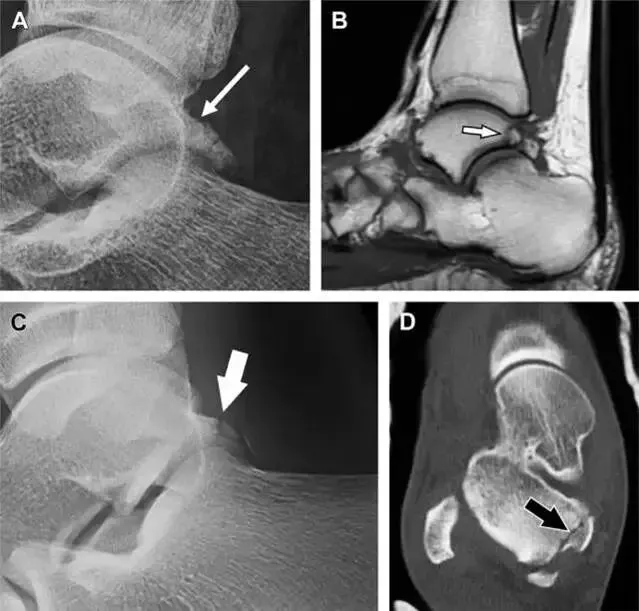

(图)距骨后突骨折。

侧位片(A)和 MRI矢状位 T1加权像。

(B)均示后外侧突的简单骨折(箭头),再次阅片时才发现 X 线片上的骨折。侧位片(C)和CT横断面图像示后内侧突的粉碎型骨折(箭头)。